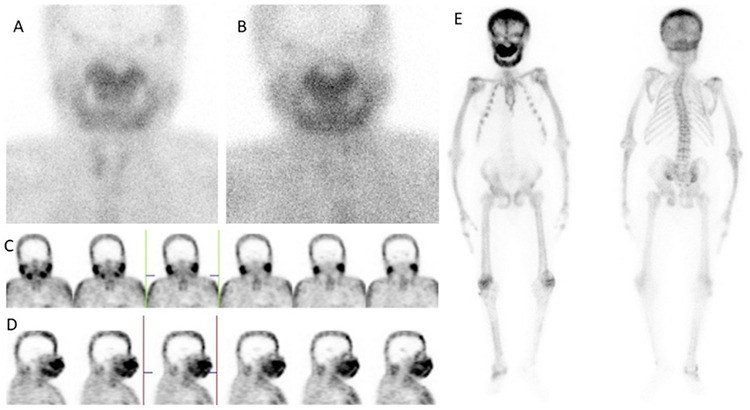

Sagliker syndrome (SS) is a rare, exaggerated form of chronic kidney disease (CKD)-mineral and bone disorder resulting from untreated secondary hyperparathyroidism due to CKD. Herein, we describe a 34-year-old male patient whose Tc-99m-methylene diphosphonate bone scintigraphy and Tc-99m-sestamibi parathyroid scintigraphy revealed hints of SS and exhibited its defining characteristics.